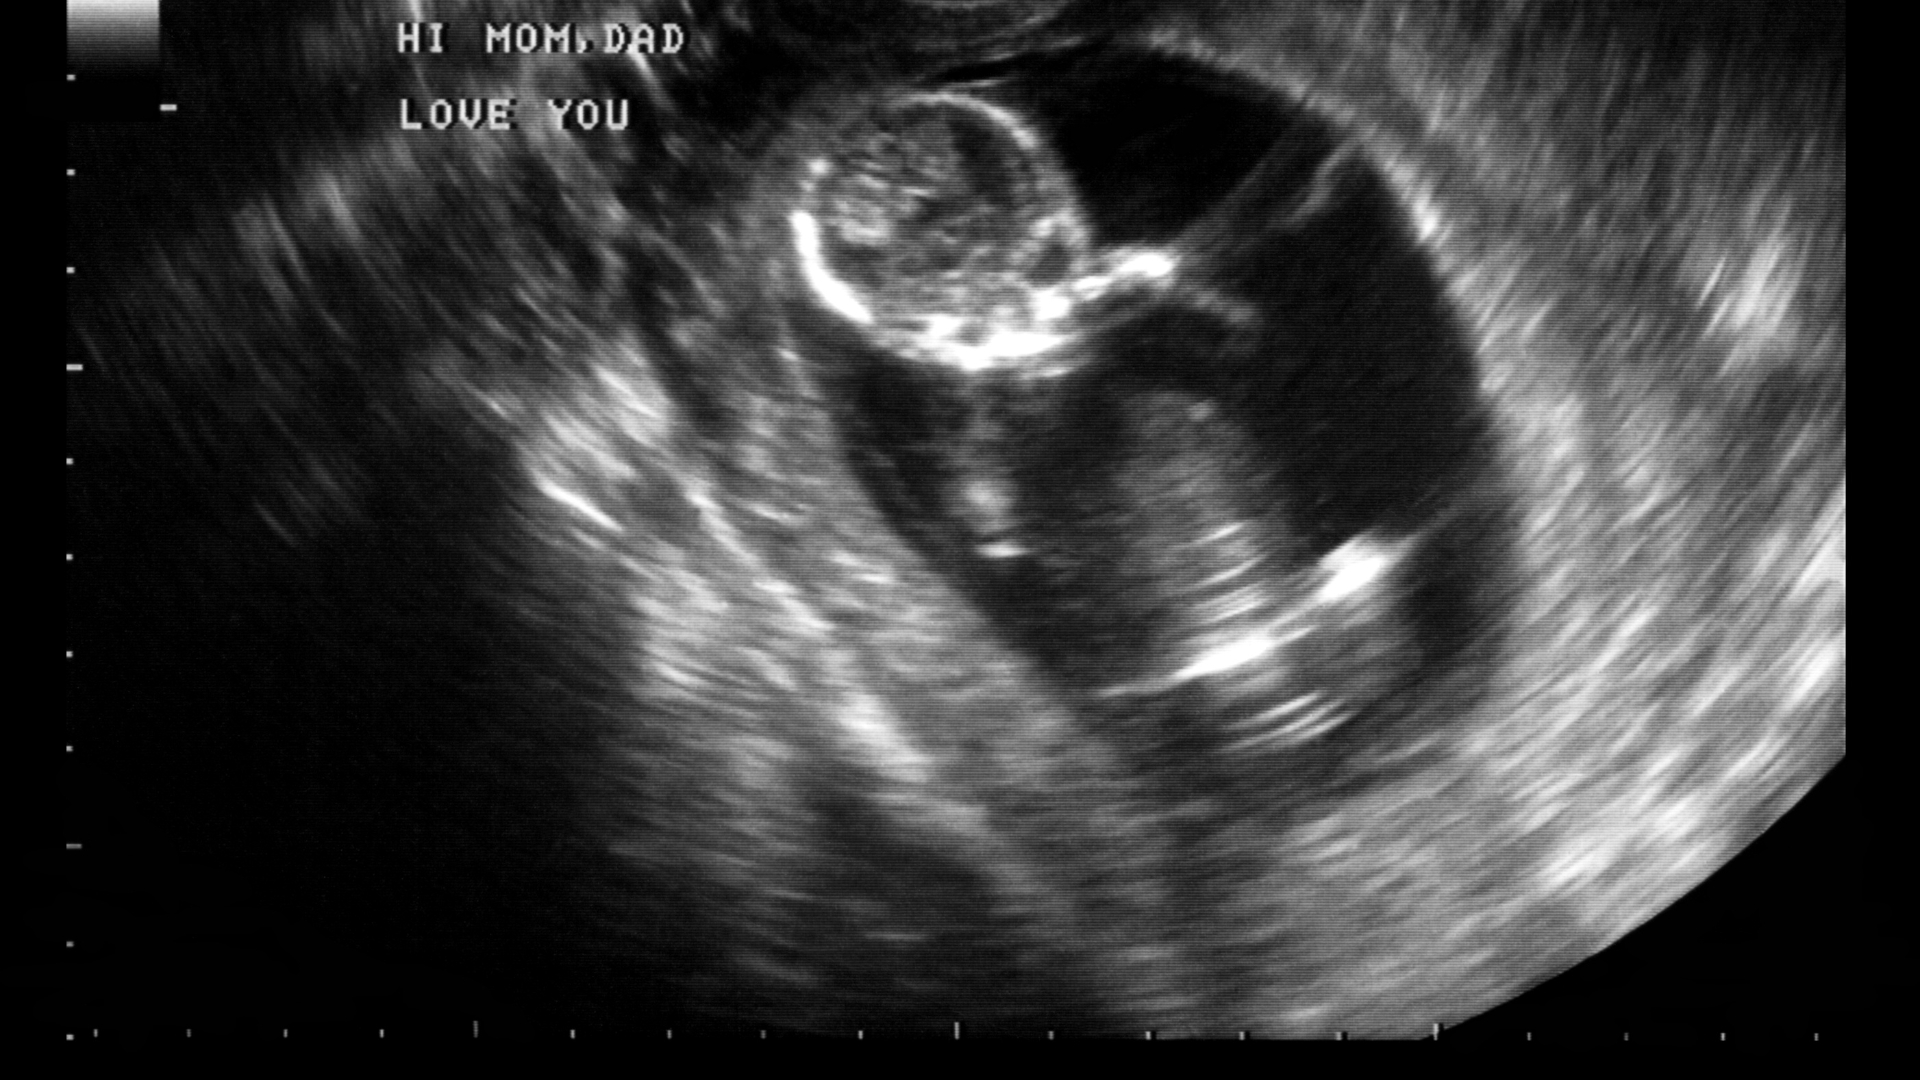

Trong tam cá nguyệt thứ hai (từ tuần 13 đến 27), hiện tượng rỉ ối tuy ít gặp nhưng lại tiềm ẩn nhiều rủi ro. Khác với vỡ ối - khi nước ối chảy ào ạt và rõ ràng - thì rỉ ối là hiện tượng nước ối thoát ra từ từ, không gây cảm giác rõ rệt mà chỉ khiến quần lót mẹ luôn ẩm ướt.

Ở giai đoạn giữa thai kỳ, màng ối chưa có dấu hiệu chuẩn bị cho sinh nên nếu bị rò rỉ, đây thường là dấu hiệu bất thường. Nếu không được phát hiện và xử lý sớm, rỉ ối có thể dẫn đến nhiễm trùng màng ối, thiểu ối hoặc nguy cơ sinh non - ảnh hưởng nghiêm trọng đến sức khỏe của thai nhi. Những biểu hiện giúp nhận biết rỉ ối: